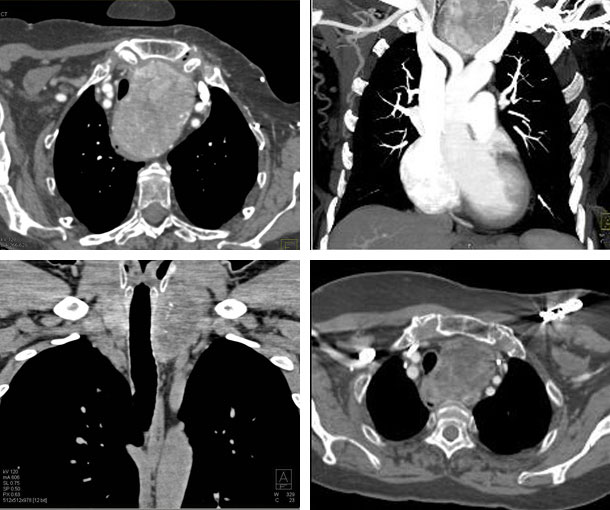

Chest CT Appearances

Substernal Goiter CT Findings

- About >50% of goiter’s volume extends below the thoracic inlet

- Most commonly extend into anterior mediastinum

- Arise from inferior pole of one thyroid lobe

- More commonly extends into right mediastinum

- Well-defined borders

- Most will contain calcifications in addition to cystic changes